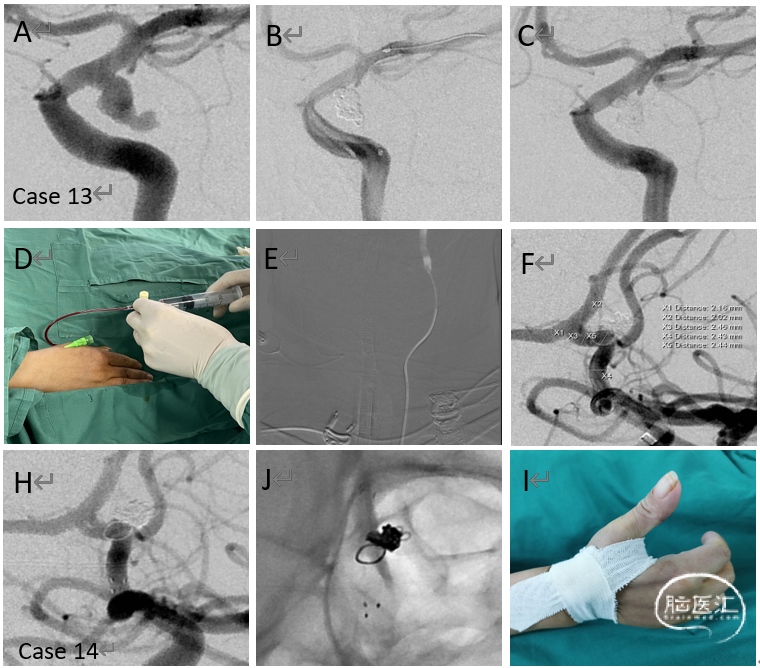

病例13-14

支架结合弹簧圈治疗后交通动脉瘤(Case 13)和经远侧桡动脉入路二期支架植入治疗破裂的前交通动脉瘤(case 14)